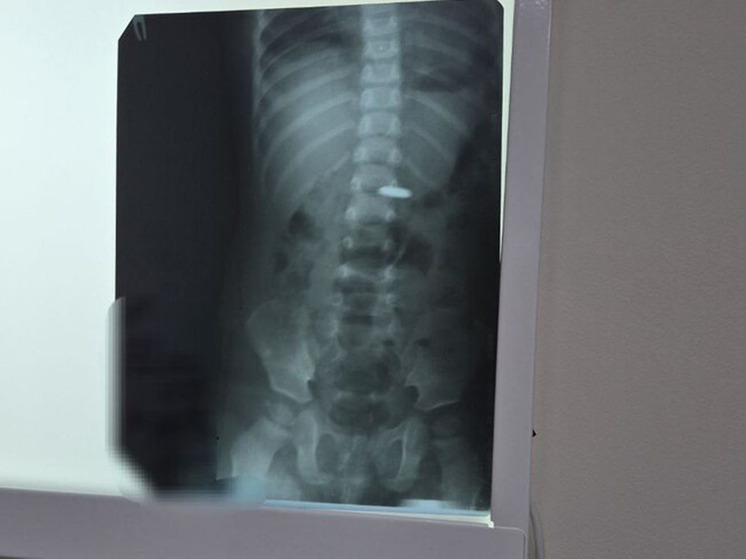

Фото: Балаковская ЦРБ

Врачи в Балакове успешно удалили батарейку из желудочно-кишечного тракта годовалого ребенка, предотвратив смертельно опасные последствия, о чем сообщает официальный телеграм-канал медицинского учреждения. Специалисты экстренно провели процедуру по извлечению элемента питания.

Медработники отмечают, что особенно высокий риск представляют батарейки, имеющие большой диаметр. Они могут стать причиной фиксации в кишечнике или застревания в привратнике желудка, что, в свою очередь, может повлечь необходимость оперативного вмешательства. Удаление инородного тела осуществляется незамедлительно с использованием эндоскопа, после того как рентгенологическое исследование подтвердит его нахождение в пищеводе или желудке.